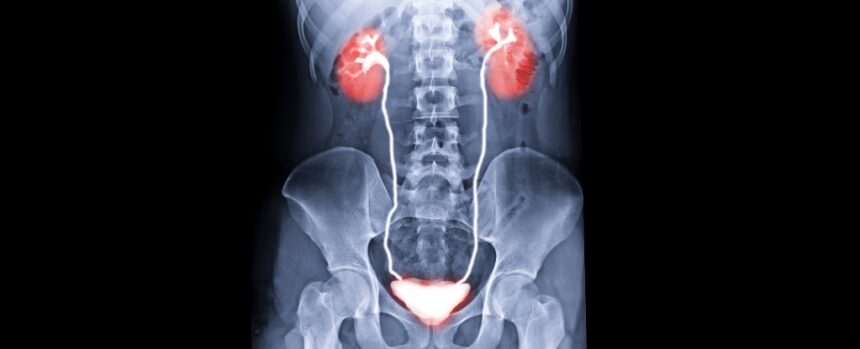

On 4 May 2025, a groundbreaking medical achievement took place as US surgeons conducted the world’s first human bladder transplant. This intricate eight-hour procedure involved the transplantation of a kidney and bladder from an organ donor into a patient who had lost these organs due to kidney disease and cancer.

The lead urologist, Nima Nassiri from the University of California, Los Angeles, stated that the transplanted kidney immediately began producing urine, leading to a significant improvement in the patient’s kidney function post-surgery. Remarkably, the patient no longer required dialysis, and the urine drainage into the new bladder functioned perfectly.

By innovatively connecting the donor bladder and kidney within a 41-year-old patient who had been dependent on dialysis for seven years, the surgeons successfully completed the transplant. The recipient, Oscar Larrainzar, who had undergone extensive bladder and kidney removal previously, experienced a significant improvement in his bladder capacity.